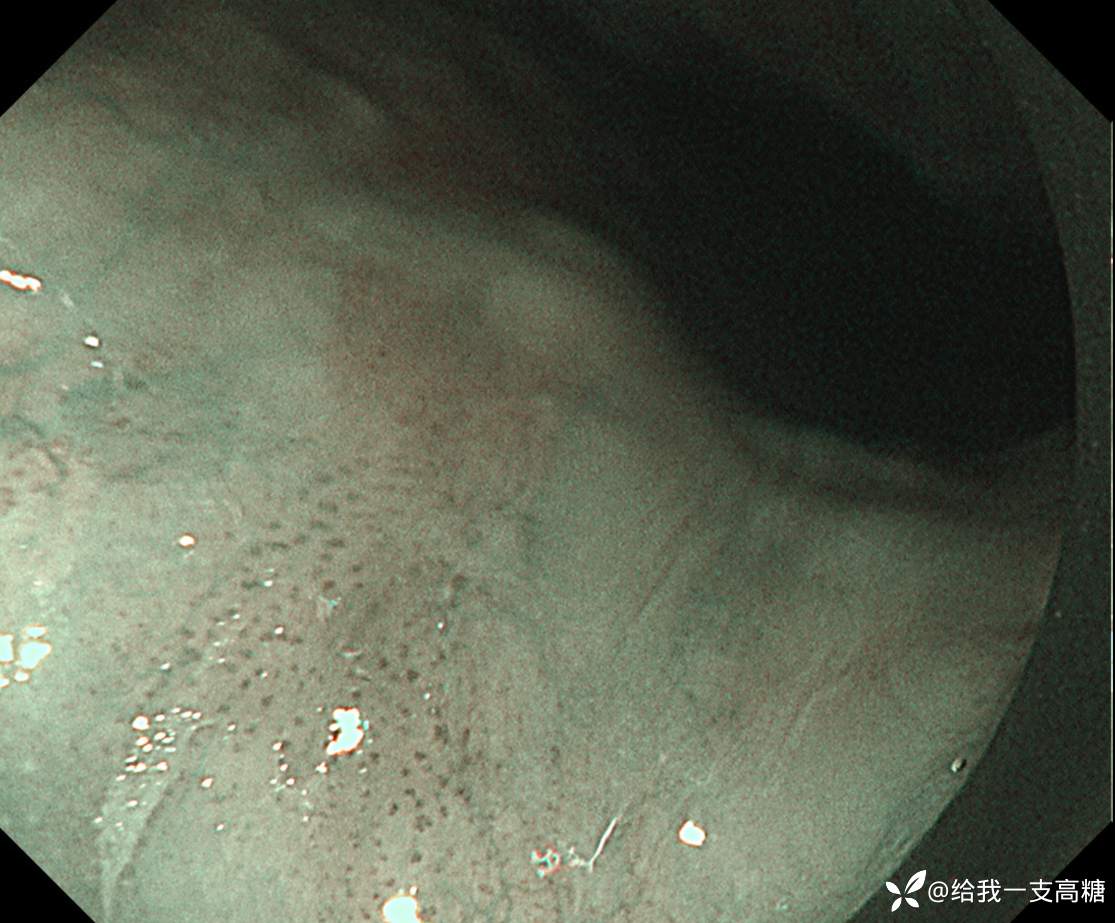

门诊体检行胃镜见食管中段黏膜粗糙,活检提示高级别,鳞状细胞为主

NBI下见局部IPCL B1